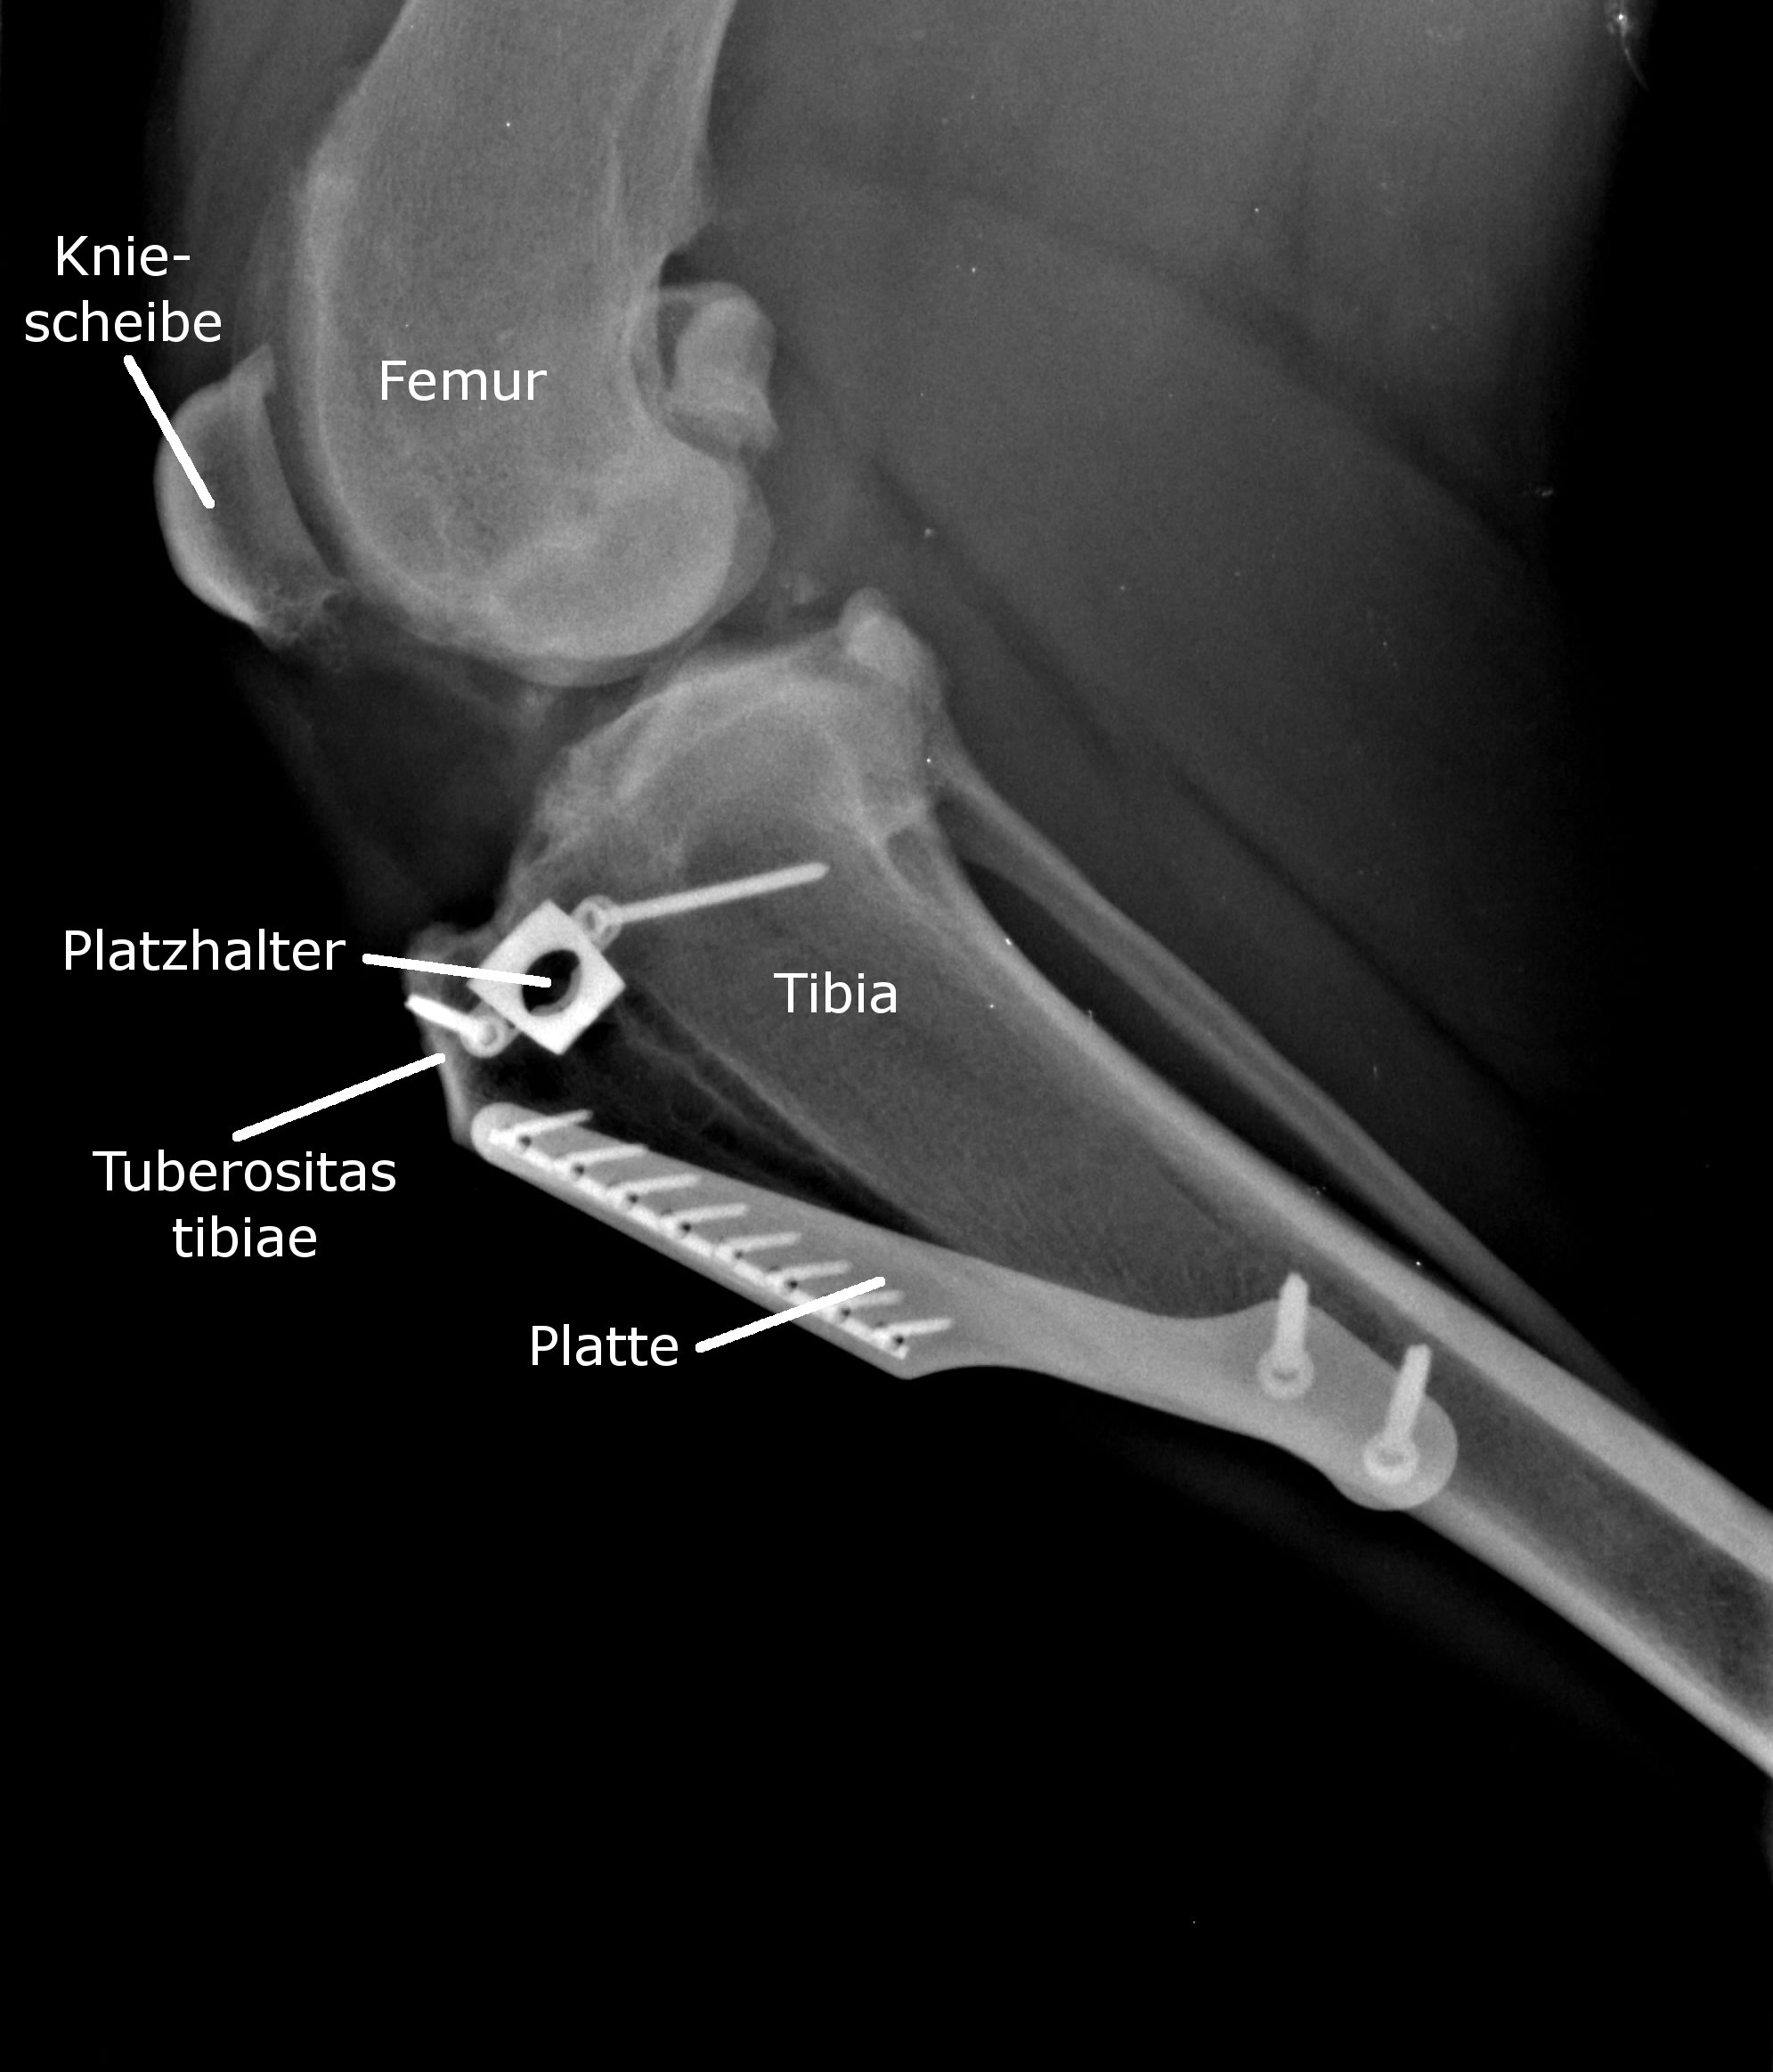

| Beim Tibial tuberosity advancement (TTA) wird ein Teil des Schienbeinknochens (die sogenannte Tuberositas tibiae) abgesägt , mit Hilfe eines sogenannten Platzhalters vorverlagert, und mit einer Metallplatte an der neuen Position fixiert. Dadurch wird der Verlauf und damit die Zugrichtung der Sehne der Kniescheibe (Patellarsehne), die an dieser Stelle ansetzt, verändert: Die Patellarsehne steht dann in einem Winkel von 90 Grad zum Tibiaplateau und kann auf diese Weise anstelle des gerissenen Kreuzbandes den oben beschrieben Scherkräften zwischen Ober- und Unterschenkelknochen entgegenwirken. |

![]() |

Nach einer TPLO kann sich der Zug auf die Patellarsehen verstärken, während die TTA diese biomechanisch eher entlastet. Bei der TPLO wird die Kongruenz, also die Übereinstimmung der Gelenkflächen vermindert, nicht hingegen bei der TTA.